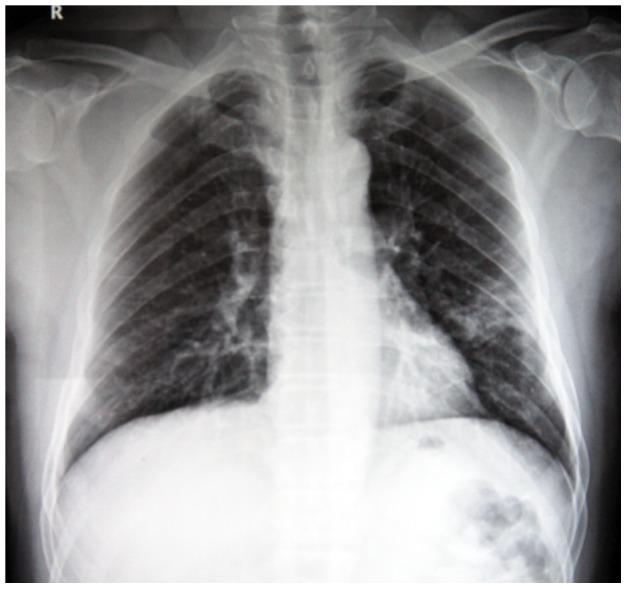

The novel H7N9 virus causes severe illness, including pneumonia and acute respiratory distress syndrome, with high rates of mortality. We investigated the association of initial radiologic characteristics obtained at admission with clinical outcomes in patients with avian influenza H7N9 pneumonia.

Demographics, comorbidities, clinical findings, radiologic appearance and scores of the affected lung parenchyma were compared between survivor group (n = 15) and mortality group (n = 7). Two radiologic scores were calculated, one using chest radiography and one using CT. Follow-up CT scans at discharge were analyzed in 12 patients of the survival group.

All the patients in mortality group developed acute respiratory distress syndrome and required mechanical ventilation, while in the survival group 33% (5/15) developed acute respiratory distress syndrome (P<0.05) and 27% (4/15) required mechanical ventilation (P<0.05). The mean radiographic and CT scores of the mortality group were 50% higher compared to the survival group (P<0.05). ROC analysis revealed an area under curve of 0.738 for the radiographic score with an optimal cutoff value of a score of 19 for prediction of mortality, with a sensitivity of 71% and a specificity of 67%, and an area under curve of 0.833 for the CT score with an optimal cutoff value of a CT score of 21 for prediction of mortality, with a sensitivity of 86% and a specificity of 73%. The mean CT score of the affected lung parenchyma at discharge was 30% lower than the initial CT examination (P<0.05).

High initial radiologic score is associated with mortality in patients with avian influenza H7N9 pneumonia.